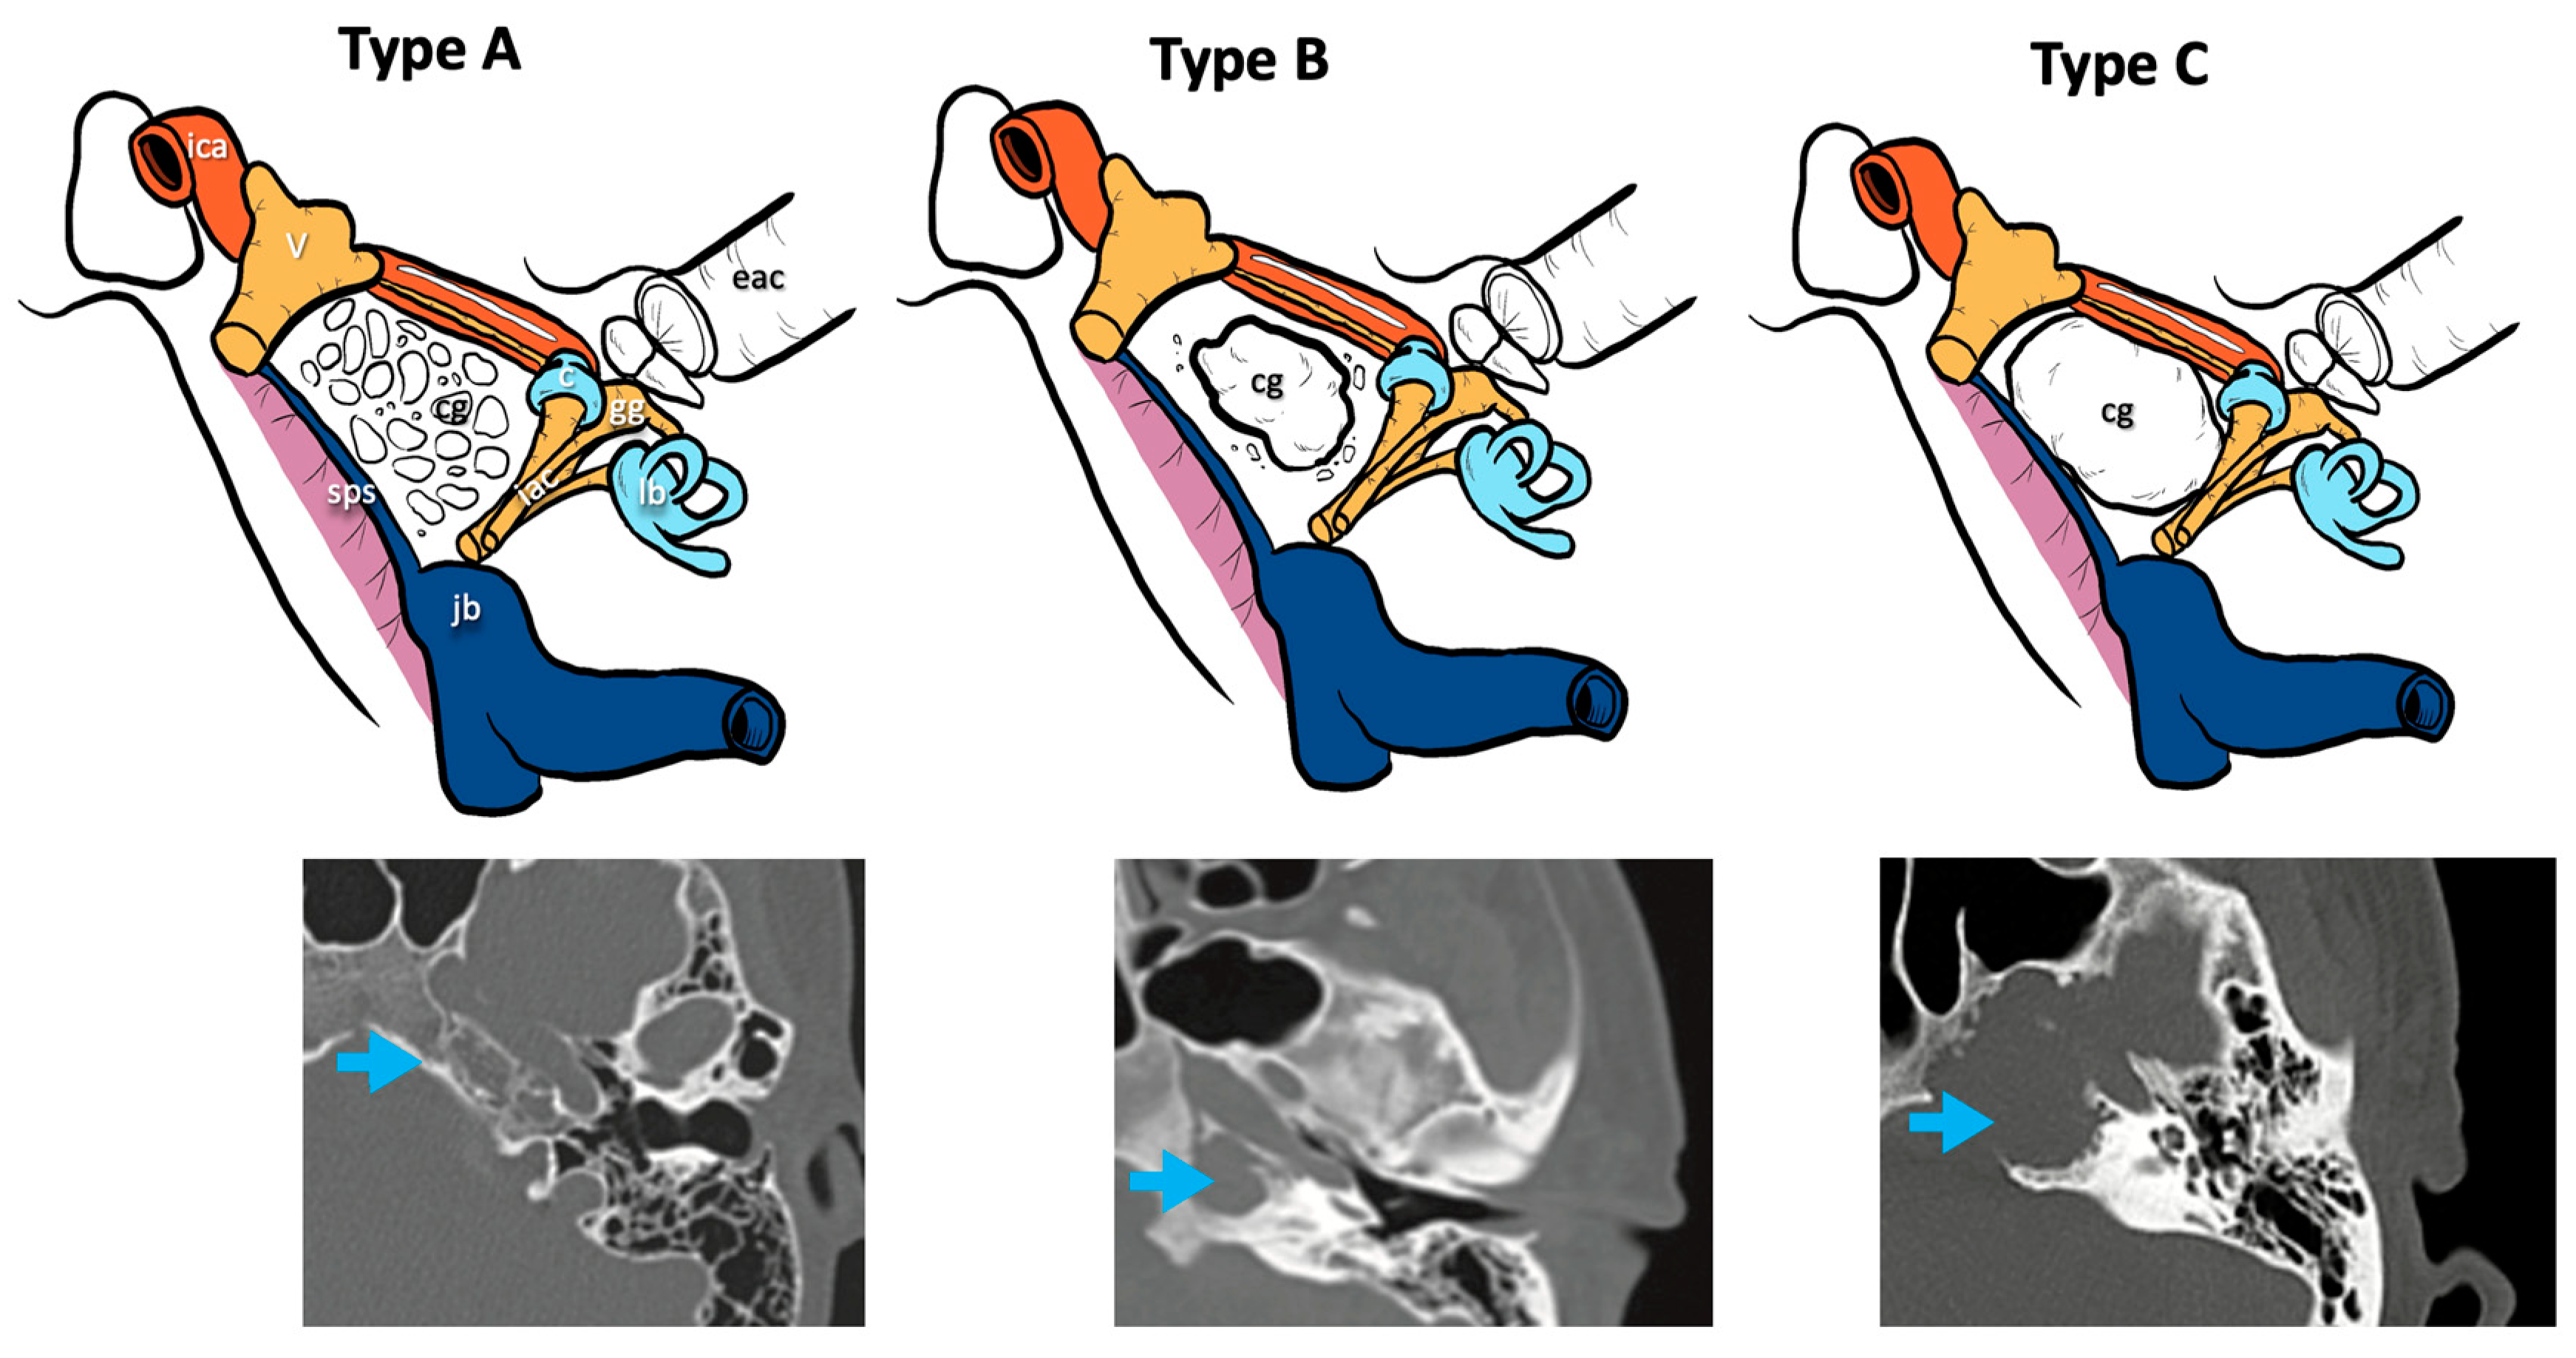

Three radiological types of cholesterol granuloma were distinguished according to the different radiological features of the petrous apex bone modifications and remodeling caused by this lesion (Figure 1):

Figure 1.

CT classification of cholesterol granulomas. V, fifth cranial nerve; ica, internal carotid artery; jb, jugular bulb; iac, internal auditory canal; lb, labyrinthine block; c, cochlea; eac, external auditory canal; gg, geniculate ganglion; sps, superior petrosal sinus; cg: cholesterol granuloma; blue arrows, cholesterol granuloma on the CT scans.

- Type A cholesterol granuloma: presence of a cholesterol granuloma of the petrous apex with preserved cellularity in the absence of erosive phenomena and/or of cellular confluence.

- Type B cholesterol granuloma: presence of a cholesterol granuloma of the petrous apex with erosive phenomena and cellular confluence without any involvement of the bony limitations that cover the noble structures of the apex (otic capsule, IAC, middle and posterior cranial fossa dura, ICA, jugular bulb).

- Type C cholesterol granuloma: presence of a cholesterol granuloma of the petrous apex with erosive and cellular confluence phenomena with involvement of the bony limitations covering the noble structures of the apex (otic capsule, IAC, dura of the middle and posterior cranial fossa, ICA, jugular bulb).